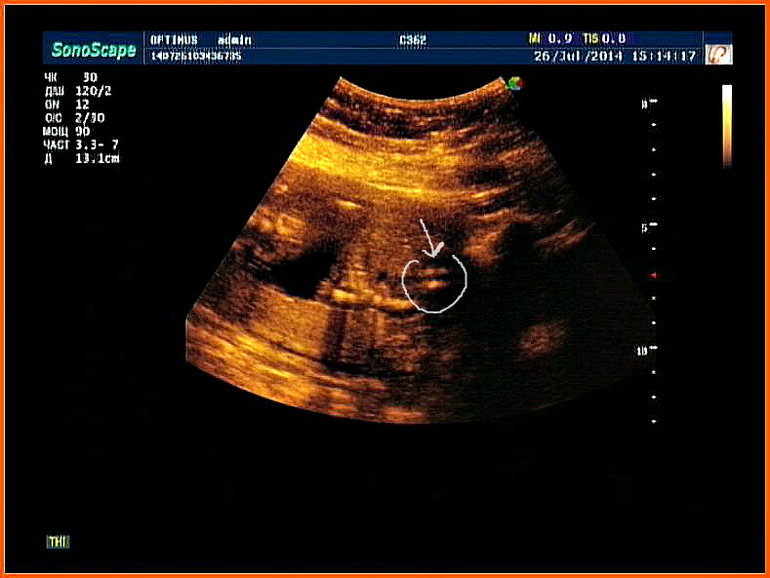

Всё о нашей беременностиразницу?))))просматривали сейчас с любимым видео нашего малыша,на котором сказали что мы доченька и увидели две разных картинки)))))))Фото под кат.

1)Тут видно женскую писюльку)))

2)а тут мужскую))))))))))или нас глючит)))))))

Фото размазаны,скрины было делать очень трудно,малышка наша крутится,вертится поэтому ни попы ни ножек не видно,но на обоих фото точно писюлька))

на первой явный пирожок,а на второй тоже пирожок,просто то клитор выпирает-у девочек он сначала большой,а потом закрывается половыми губками....

на первом фото большие полоые губы, на втором немного сдвинут ракурс кпереди и виден клитор и опять же большие половые губы)))у мальчиков не только "3-я нога", как пишут ниже, но и мошонка, которую при таком ракурсе оч.трудно спутать))))